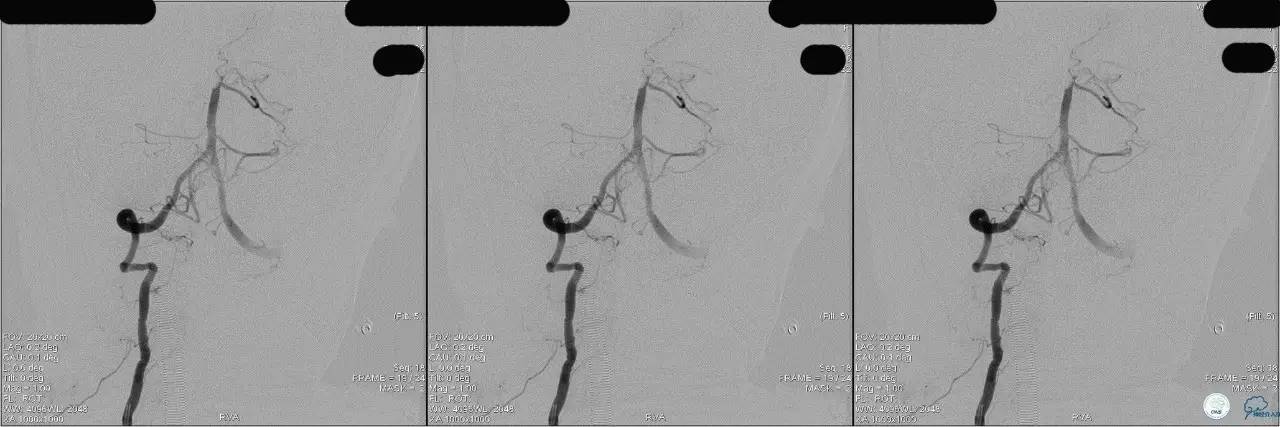

》DSA资料(第3次取栓后,发病10h)

》DSA资料(观察30min后,左椎造影)